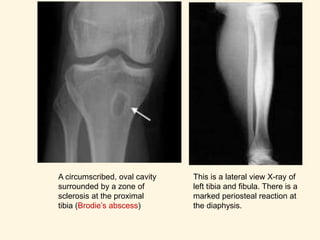

 A circumscribed, round/oval cavity containing pus and

pieces of dead bone (sequestra) surrounded by

sclerosis.

 Most commonly seen in tibial / femoral metaphysis.

A circumscribed, oval cavity

surrounded by a zone of

sclerosis at the proximal

tibia (Brodie’s abscess)

This is a lateral view X-ray of

left tibia and fibula. There is a

marked periosteal reaction at

the diaphysis.